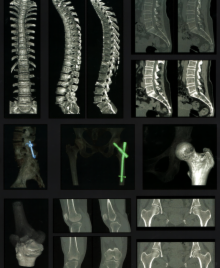

脊椎などの骨部

単純CT

3DCT(subtraction可能)

脊椎 T1画像、T2画像

T2*画像

脂肪抑制画像

造影MRI

ミエログラフィー